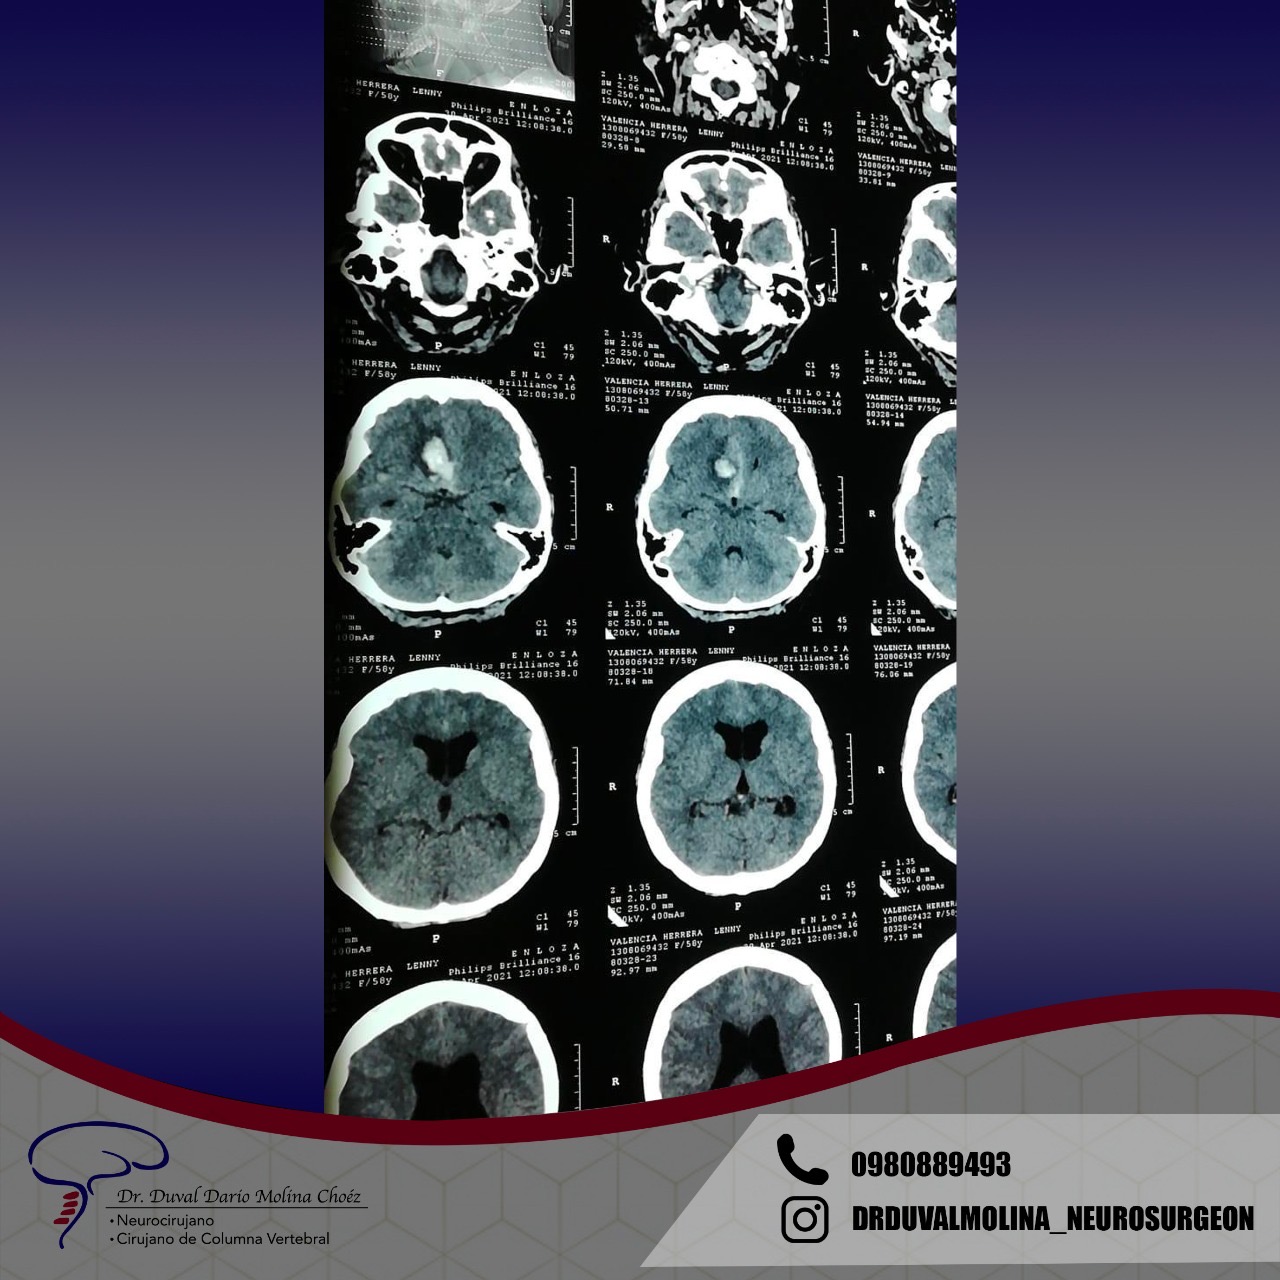

Un Glioma que causa efectos de compresión y «edema»(inflamación)

Metástasis (cáncer)

Cuando un tumor primario se disemina desde su sitio de origen, normalmente lo transporta el torrente sanguíneo. El cerebro es un sitio importante para los depósitos secundarios y estos tumores tienen un aspecto característico en la resonancia magnética. A menudo causan una inflamación cerebral sustancial. Si se desconoce el sitio primario o si una o más lesiones son sintomáticas y accesibles, generalmente se recomienda la extirpación quirúrgica.